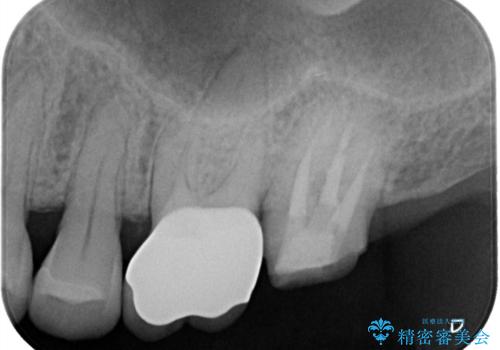

レントゲン上にて、左上6番遠心にインレーと歯質の不適合を認めます。

健全歯質の残存量から、クラウンでのやり替えを提案しオールセラミッククラウン(スタンダード)でのやり替えとなりました。

・オールセラミッククラウン(スタンダード) 121,000円(税込み)